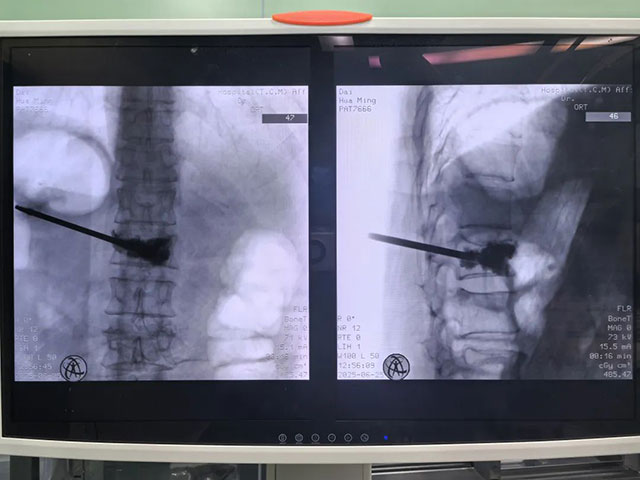

经过影像学检查,诊断迅速明确:L3椎体压缩性骨折!

x片

微创手术(骨水泥灌注):通过局麻小切口向伤椎注入 “骨水泥”,十分钟即可硬化定型,恢复椎体稳定性。术后第一天就能下地,大幅减少卧床风险。

最终,王奶奶选择了微创手术。手术不到半小时就结束,术后疼痛明显缓解,一周后顺利出院。